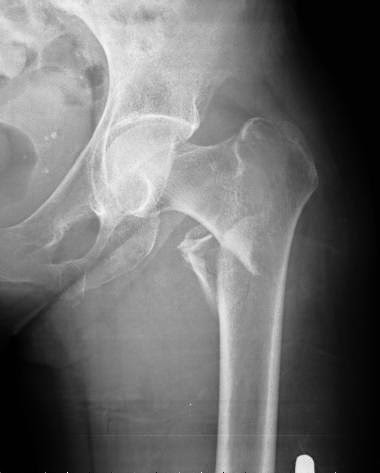

Osteoporosis: umbrales de intervención adaptados a cada país

Una revisión sistemática de los umbrales de intervención basados en la herramienta FRAX para la estimación del riesgo de fractura. Archives of Osteoporosis, 27 de julio de 2016